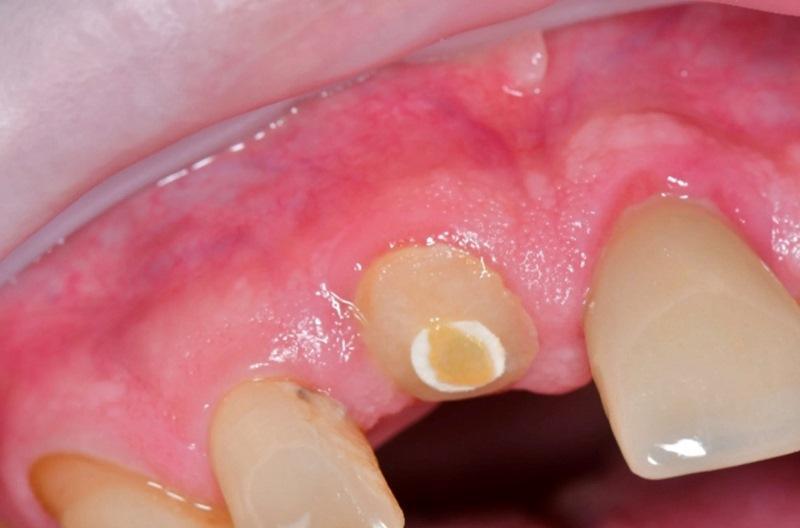

Забрана кровь пациента для получения лейкоцитарного обогащенного тромбоцитами фибрина (L-PRF). Местная анестезия выполнена со стороны щеки и неба в области удаляемого зуба. Периотомом проведено отделение десневого прикрепления от зуба. Корень зуба 1.1 вывихнут элеваторами и атравматично удален универсальным пинцетом. Лунка выскоблена и санирована с удалением грануляций. Проведено обильное орошение стерильным физиологическим раствором. Зондом исследованы стенки лунки на предмет дефектов; таковые не обнаружены, лунка интактна.

Хирургический шаблон введен в полость рта для проверки посадки относительно соседних зубов и стабильности на дуге. Остеотомия выполнена с применением направляемого хирургического набора (Ritter Guided Kit, Ritter Implants) через шаблон для немедленной установки имплантата в область зуба 1.1. Стартовая остеотомия выполнена пилотным сверлом 2,8 мм из направляемого набора (Ritter Implants), введенным через шаблон для обеспечения точной ориентации и позиционирования. Далее проведена оссеоденсификация борами Densah (Versah), в частности 3,0 и 3,5 мм, в обратном режиме (против часовой стрелки) согласно протоколу производителя, при 1 200 об/мин с обильной ирригацией физиологическим раствором. Имплантат (Spiral SB/LA Implant, 4,2×13 мм, Ritter Implants) установлен через хирургический шаблон в полости рта с позиционированием на 3 мм ниже уровня гребня. Вкручивание достигнуто при моменте 25 Н·см. Индивидуальный формирователь десны подготовлен и отложен до этапа установки.

Аллотрансплантат MinerOss (BioHorizons) смешан с PRF, полученным в начале приема, для изготовления смеси «липкая кость». Смесь введена для заполнения гребневых щелей между стенками лунки и имплантатом. Затем на имплантат установлен индивидуальный формирователь десны.